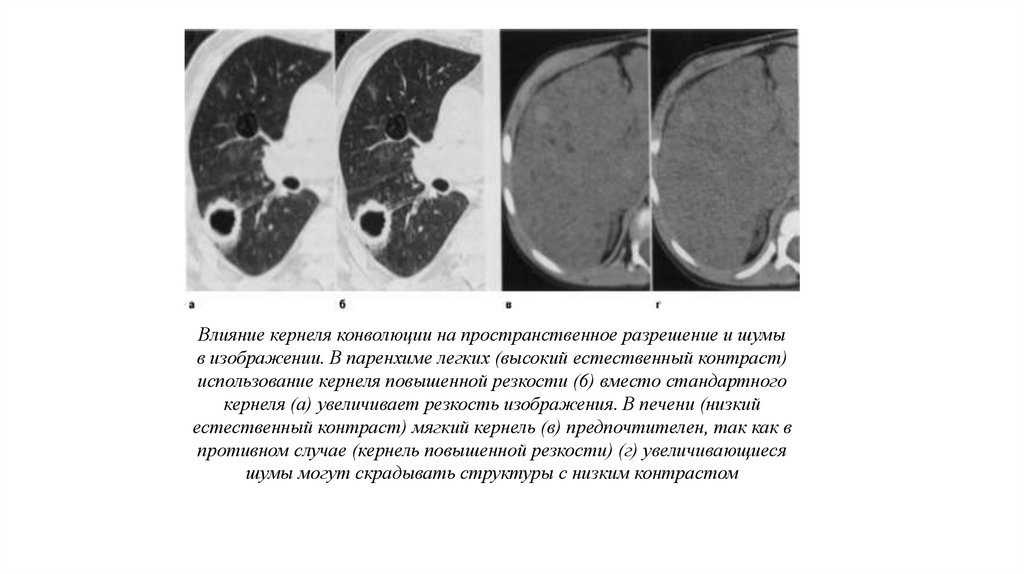

Влияние кернеля конволюции на пространственное разрешение и шумы

в изображении. В паренхиме легких (высокий естественный контраст)

использование кернеля повышенной резкости (6) вместо стандартного

кернеля (а) увеличивает резкость изображения. В печени (низкий

естественный контраст) мягкий кернель (в) предпочтителен, так как в

противном случае (кернель повышенной резкости) (г) увеличивающиеся

шумы могут скрадывать структуры с низким контрастом